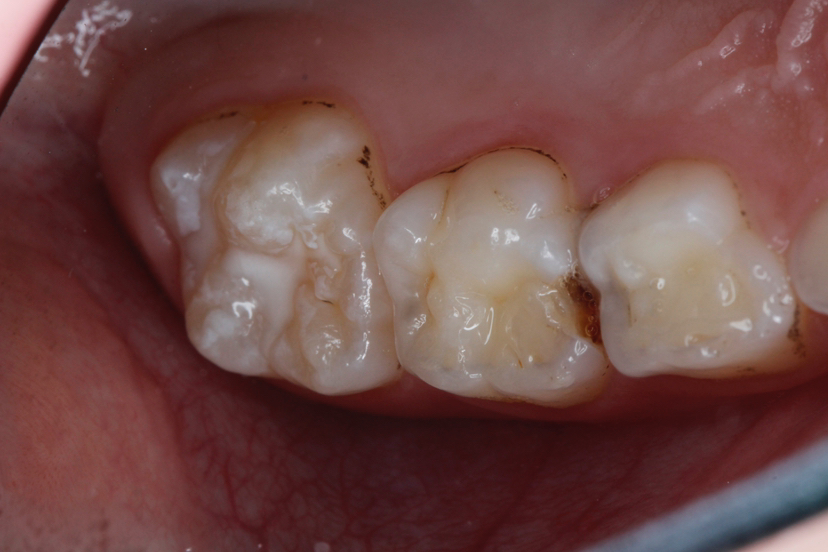

牙齿的咬合面布满了深浅不一的窝沟,这些细小的缝隙最容易藏匿食物残渣和细菌。儿童由于刷牙技巧不够熟练,很难彻底清洁这些部位。窝沟封闭技术就是将一种特殊的树脂材料涂布在牙齿表面,形成一层保护膜,将窝沟封闭起来,阻止细菌和食物残渣的侵入。

临床研究数据显示,经过窝沟封闭的牙齿,龋齿发生率可降低80%以上。这种预防效果远远超过普通的刷牙和漱口。封闭剂能够持续保护牙齿数年,直到孩子的口腔卫生习惯完全建立。